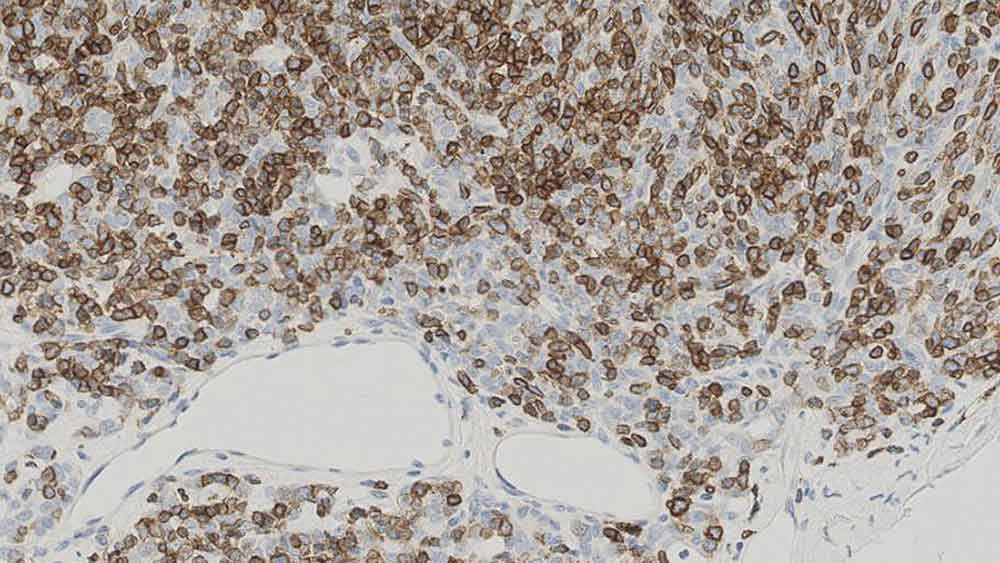

Human placenta: immunohistochemical staining with Human Chorionic Gonadotrophin (beta): Polyclonal

HCGp was raised to the isolated beta-chain of human chorionic gonadotrophin and reacts with placental trophoblasts. HCGp shows a slight cross-reaction with luteinizing hormone and may, therefore, stain basophil cells in the pituitary.

Human Chorionic Gonadotrophin (beta) is recommended for the detection of specific antigens of interest in normal and neoplastic tissues, as an adjunct to conventional histopathology using non-immunologic histochemical stains.